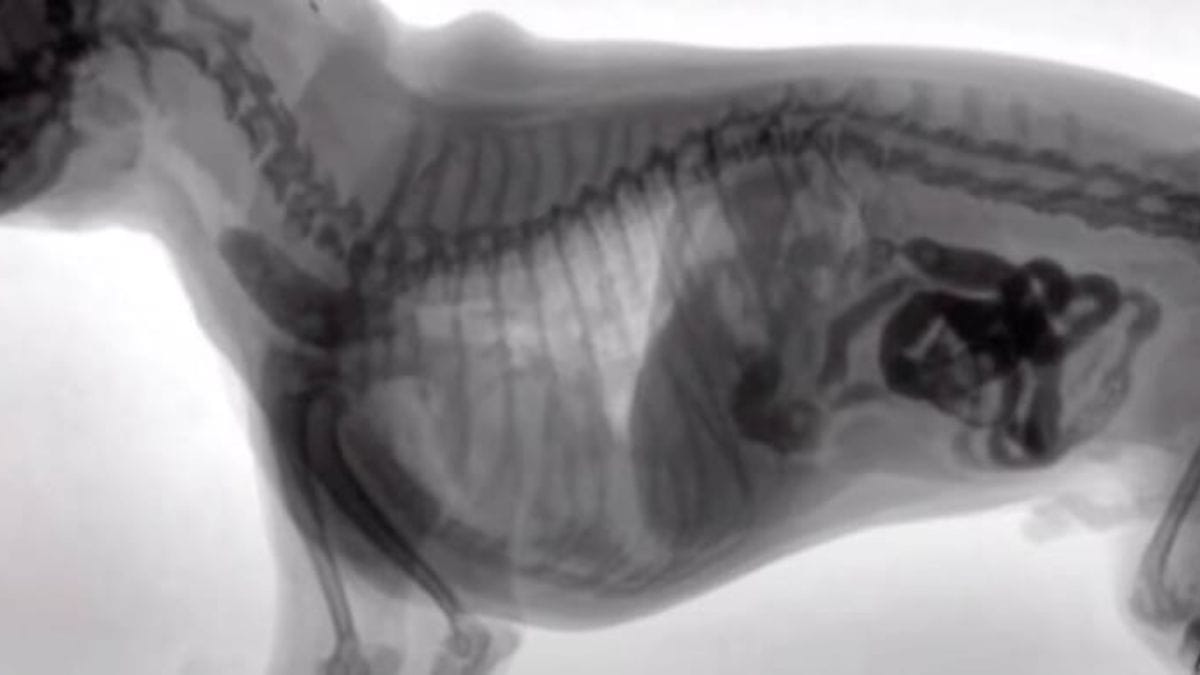

Il veterinario vede cosa ha ingoiato il suo cane: il proprietario muore di vergogna